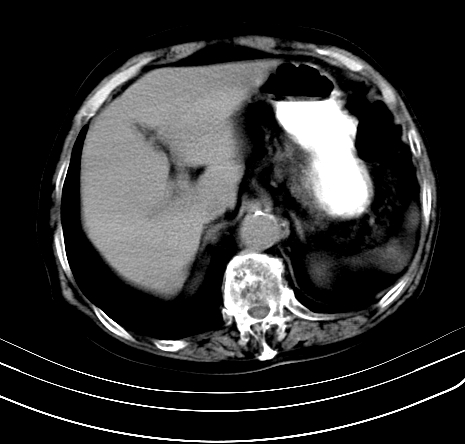

上腹部疼痛不适,行ct检查

胰腺明显肿大,密度减低,考虑慢性胰腺炎,假性囊肿形成不除外。

胰腺明显肿大,考虑慢性胰腺炎假性囊肿形成,不除外胰腺癌可能。

胰腺较明显扩大,胰周有渗出;肾周筋膜有增厚渗出,以左肾为著。应考虑急性胰腺炎。

慢性胰腺炎,假囊肿形成,脂肪肝。